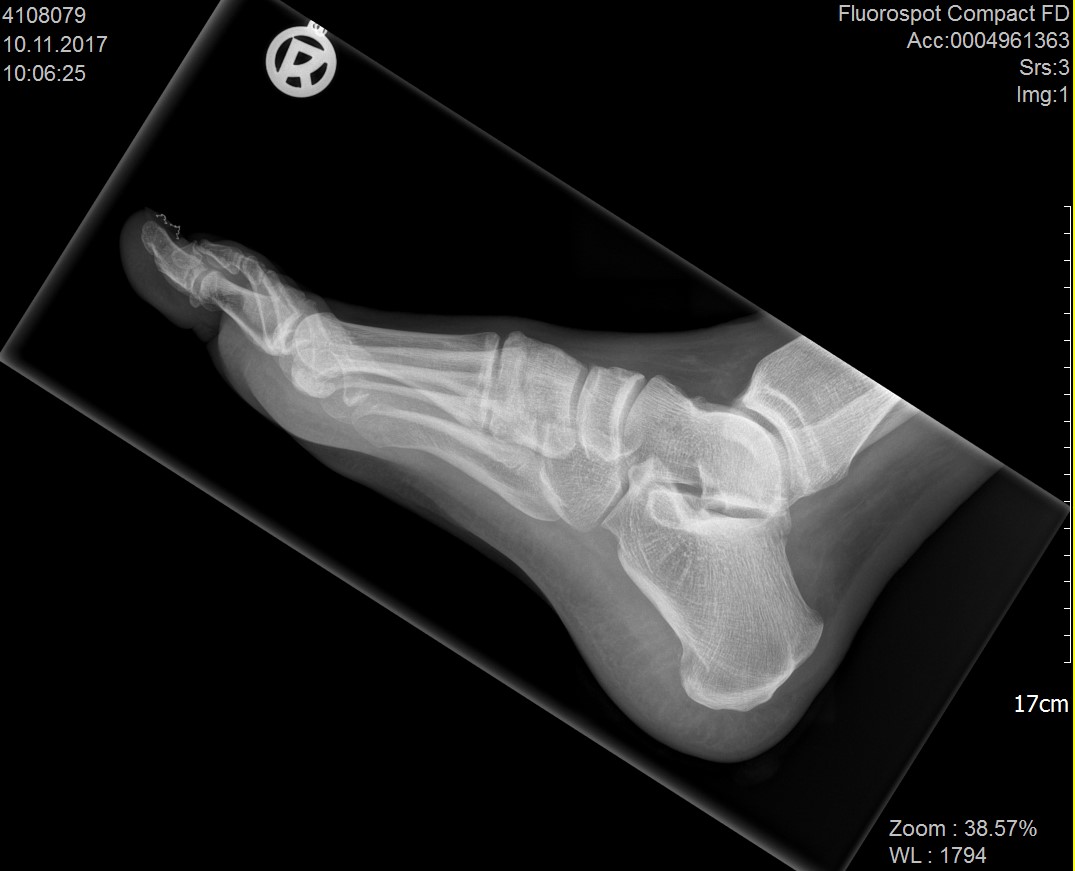

Abbildung 1: Plantarer und dorsaler Sporn im Röntgenbild und im MRT

Abb. 1a und Abb. 1b: großer dorsaler Fersensporn und ein minimaler plantarer Sporn, Patient, 50 Jahre.

Abb. 1c: Bild eines isolierten großen plantaren Fersensporns. Patientin, 32 Jahre.

Zum Lesen der Bildbeschreibung und zur Vollansicht bitte die Bilder anklicken. Bilder: Manfred Thomas.